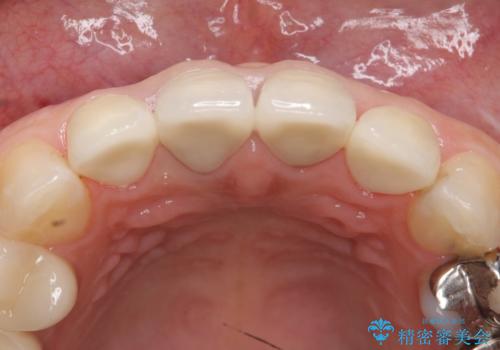

- 上顎の前から2番目の歯の古い樹脂をセラミックにしたいといらっしゃった方の症例です。

古い樹脂を除去後、オールセラミッククラウンによる補綴を行いました。

今回用いたオールセラミッククラウンはジルコニアフレームという白い素材の上にセラミックを盛っているため、審美性が非常に高いのが特徴です。